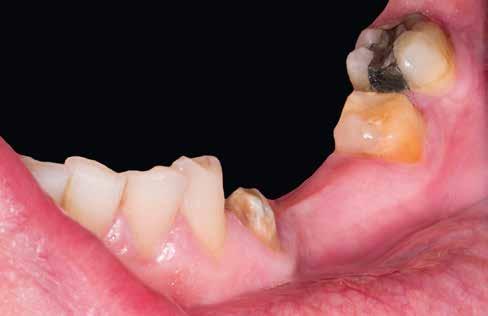

1–2. képek: Kiindulási helyzet.

Kiindulási helyzet

A páciens látlelete a következő:

• krónikus általános parodontitis

• a 24-től terjedő parodontális fekély

• hatástalan kapcsos felső fogpótlás (1-2. képek)